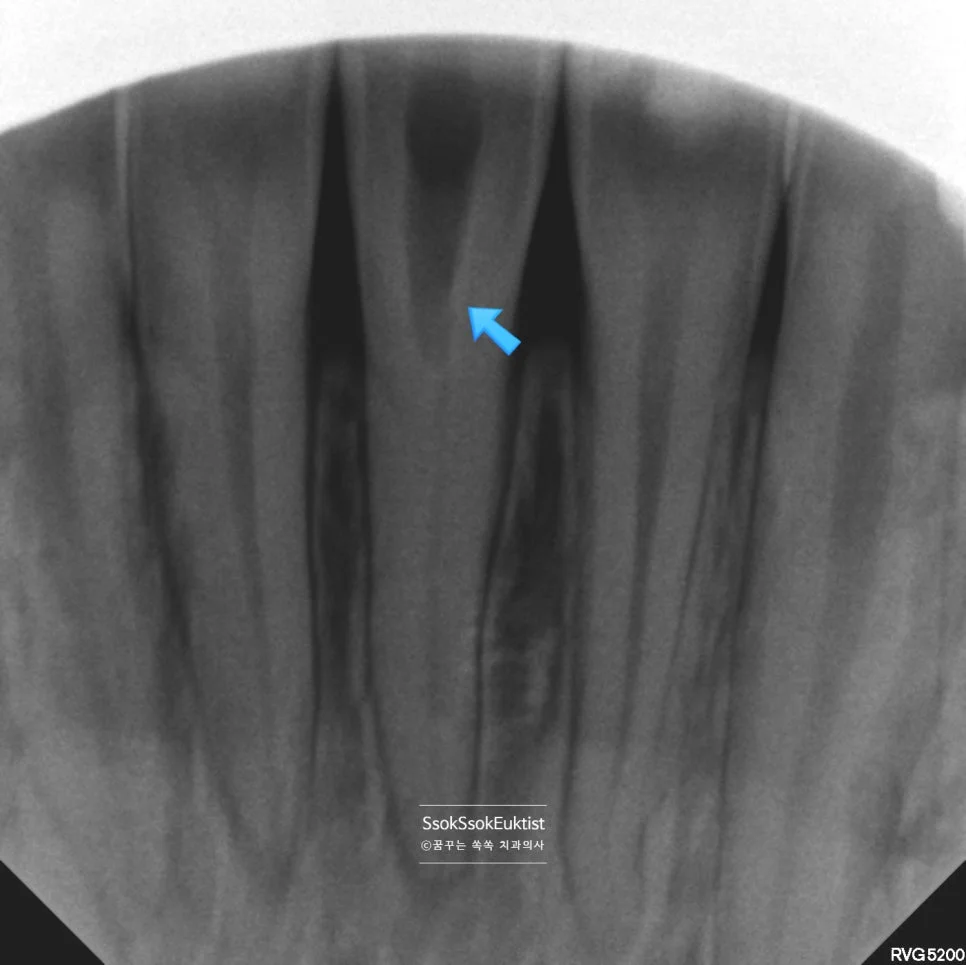

치료 중 X-ray — 안전한 위치에서 신경관 접근 방향 확인

처음 어느 정도 안전한 위치에서 접근하면서 X-ray를 촬영해 봅니다. 실제 신경관의 위치로 술자가 잘 삭제하고 있는지 확인하기 위해서인데요.

사진을 보면 어느 정도 맞는 방향으로 접근하고 있는 걸 볼 수 있습니다. 이제부터는 정말 조심히 접근하여 신경관을 찾아야 합니다. 땀을 삐질삐질 흘려가며 조심히 접근을 합니다.